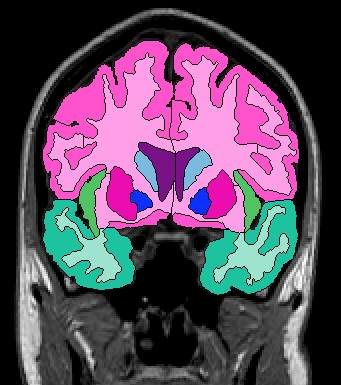

The insular cortex is “hidden” between the temporal and inferior parietal corticies. By drawing sulci lines in the sagittal view, we gain an outline of it in the coronal. Choose a sagittal slice where insula is clearly visible (Fig 1), then draw a “circle” around it (Fig 2). Do this for several slices and for both hemispheres.

Figure 1              Figure

2

Once you have drawn your sulci lines, the insula should be clearly outlined (by little dots) in the coronal view (Fig 3). This is particularly useful in the more anterior slices.

Figure 3